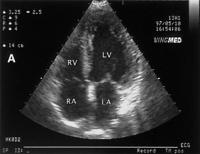

Abbildung 3a: Transthorakale Kontrast-Echokardiographie (apikaler 4-Kammer-Blick) mit dem rechten Vorhof (RA), rechten Ventrikel (RV), linken Vorhof (LA) und linken Ventrikel (LV) eines Patienten mit HPS. (A): Vor der Applikation des Kontrastmittels (geschüttelte Kochsalz-Lösung); (B): Passage der Microbubbles durch den rechten Vorhof und rechten Ventrikel; (C): Sichtbarwerden der Microbubbles im linken Vorhof und linken Ventrikel, 6 Herzschläge nach der Passage durch den rechten Vorhof/rechten Ventrikel.

Keywords: EchokardiographieHepatologieHepatopulmonales SyndromHPS